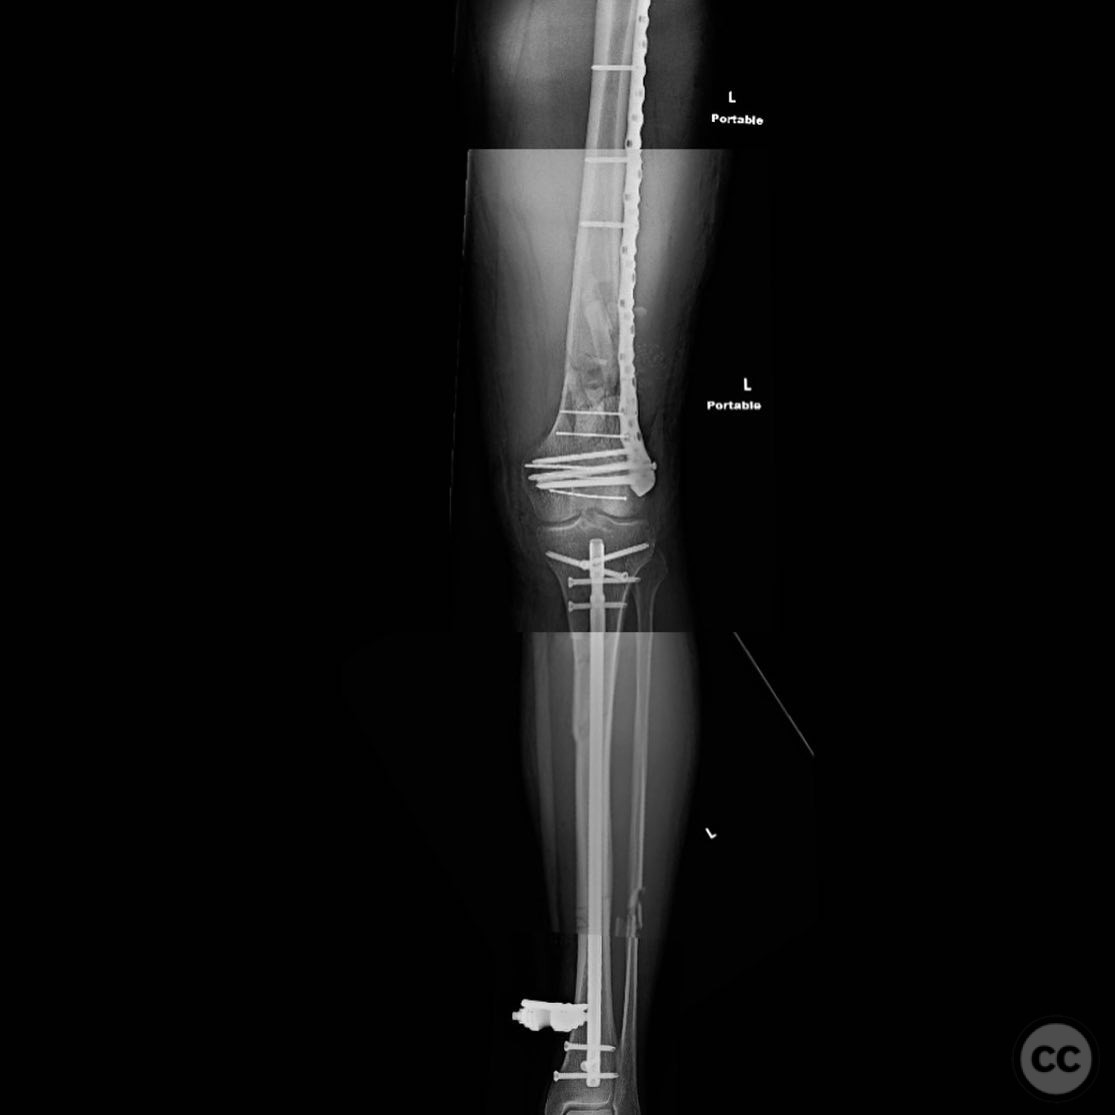

Patient positioning:  Supine positioning on a radiolucent table to facilitate fluoroscopic imaging. The affected limb was prepared for access to both the femur and tibia.

Anatomical surgical approach:  For the tibia, a longitudinal incision was made to access the proximal tibial start site for intramedullary nailing. Percutaneous clamps were utilized for reduction, supplemented by blocking screws as needed. For the distal femur, an external fixator was applied initially, followed by an in situ lateral approach for plating after reduction was achieved.

Operative remarks:

The tibial nailing required precise identification of the start site under fluoroscopic guidance, with percutaneous clamps aiding in reduction. Blocking screws were considered but not necessary due to successful reduction with clamps alone. The distal femur presented challenges in achieving coronal and sagittal alignment, necessitating reliance on the external fixator for reduction before proceeding with plating.

Postoperative protocol:   Postoperative rehabilitation included early mobilization with weight-bearing as tolerated on the tibia, while the femur required protection until definitive fixation was achieved. Progressive weight-bearing was introduced following femoral plating.

Orthopaedic implants used:   Intramedullary nail for tibia, external fixator for initial femoral stabilization, and locking plate for definitive femoral fixation.